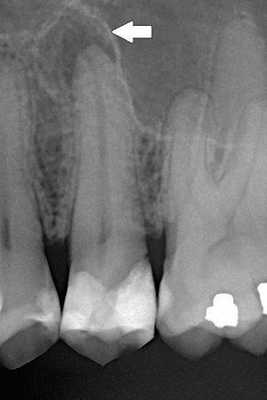

Реакции на холод не было. При электроодонтодиагностике (ЭОД) зуб реагировал на ток выше 100 мкА, что говорит о возможном периодонтите.

- сделали рентген-снимок, который показал, что корневые каналы запломбированы однородно до физиологической верхушки;

В июле 2021 года рентген показал, что разрушение костной ткани у верхушек корней зуба 1.6 уменьшилось. Мужчина отметил, что чувствует себя хорошо, боль прошла. Корневые каналы были качественно закупорены, анатомическая форма и функции зуба восстановлены.